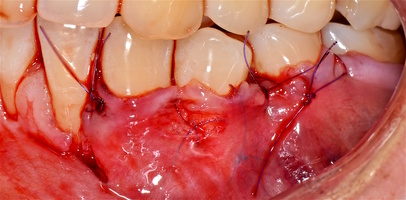

4. Фиксация пластического материала ТМО (dura mater) к поверхности корней зубов в области зоны создания необходимого объема прикрепленной десны.

5. Закрытие пластического материала слизисто-надкостничным лоскутом со смещением в корональном направлении, и фиксация слизисто-надкостничного лоскута швами; дополнительная фиксация зоны перемещенных и в будущем созданных мягких тканей десны в зоне рецессии десны для стабилизации результата операции.

Деэпителизация анатомических сосочков, обработка поверхностей корней зубов, фиксация свободного десневого аутотрансплантата и пластического материала ТМО (dura mater) швами, с полным перекрытием слизисто-надкостничным лоскутом, фиксация швами слизисто-надкостничного лоскута узловыми одиночными швами в области установки аутотрансплантата и ТМО (dura mater), двойными обвивными для слизисто-надкостничного лоскута, и крестообразными прижимающими горизонтальными швами для фиксации слизисто-надкостничного лоскута в новом положении. Обработка поверхностей корней зубов проводилась аналогично.